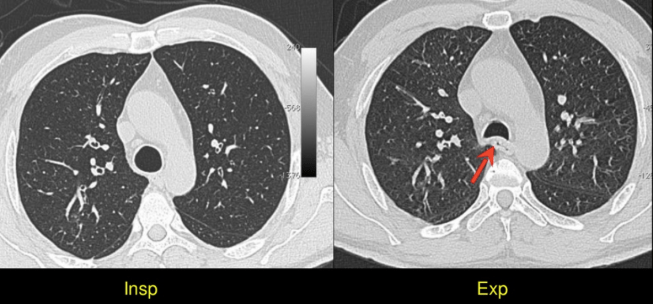

3. One way to confirm whether the CT has been obtained in inspiration or expiration is by observing the contour of the trachea. The trachea is round and expanded in inspiration, and collapsed and crescent shaped in expiration.

5. HRCT images should always be obtained in maximum inspiration as well as in end expiration.